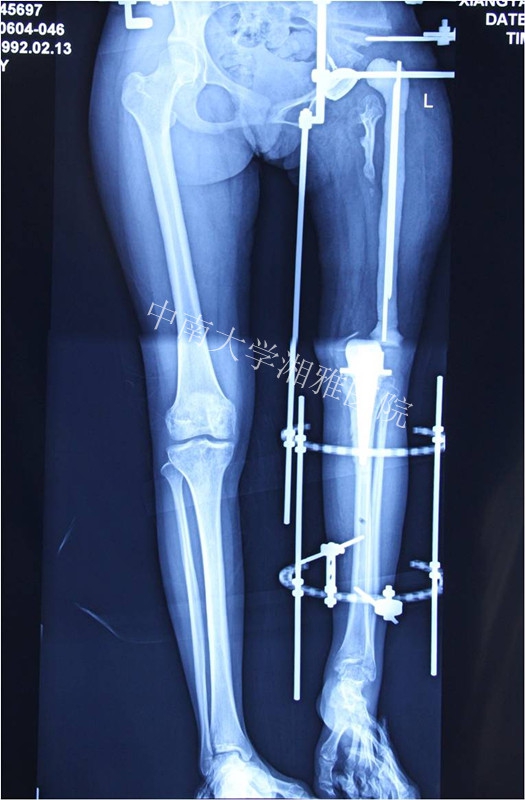

2013年10月复查双下肢长度恢复

Final Game—2013年10月